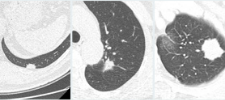

CT features of visceral pleural invasion are not independent prognostic factors in clinical T1 lung adenocarcinomas; upstaging from clinical T1 to T2 for lung cancers that contact the pleura or exhibit pleural tags on CT scans is not an evidence-based practice.